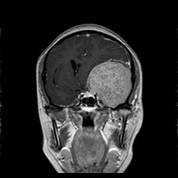

经查体,神经外六科吴杰主任诊断为:左侧蝶骨嵴占位性病变,考虑脑膜瘤可能性大。之后黄女士完善了相关检查,颅脑CT及CTA检查提示:左侧中颅窝底巨大占位病变,其内血管丰富,临近左侧大脑中动脉明显受压向上移位,考虑脑膜瘤;颅脑磁共振提示:左侧前中颅窝底巨大占位性病变,考虑脑膜瘤。介入栓塞提示:肿瘤主要由左侧脑膜中动脉额支、少量由左侧眼动脉脑膜支参与供血。

术前MRI可见左侧额颞巨大占位,增强均匀强化,考虑脑膜瘤